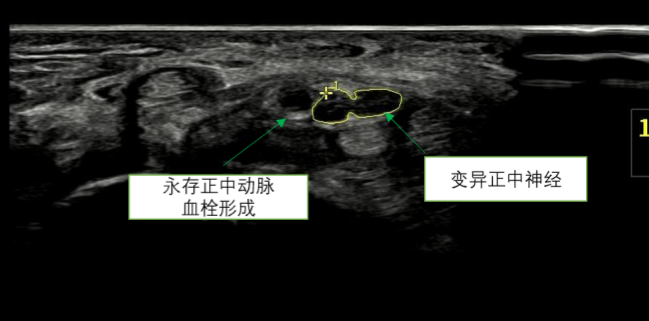

▲术前超声显示:永存正中动脉血栓形成,正中神经变异

患者为19岁男性,既往有腕部不适史,1周前无明显诱因突然出现右手掌桡侧半剧烈疼痛、麻木,保守治疗无效后来我院就诊。医院超声诊疗科方方医生诊断为“永存正中动脉合并血栓形成”。患者由手足显微外科崔宜栋医生收治入院,经进一步检查,确诊为永存正中动脉血栓致急性腕管综合征。鉴于患者右手掌桡侧半疼痛剧烈且持续不见好转,具备手术指征,手足显微外科崔宜栋医生团队在臂丛麻醉下为患者实施“正中神经松解+永存正中动脉血栓段切除术”。术后患者恢复顺利,疼痛症状消失,麻木显著减轻。